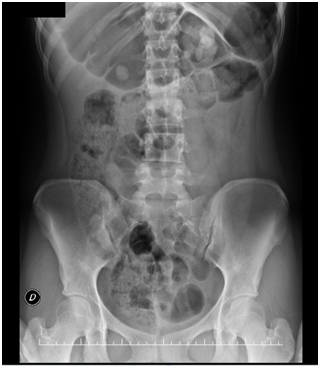

A 16 year-old girl complaining of chronic constipation and abdominal bloating since early childhood presented in the emergency department with a 36-hours of abdominal pain. The plain abdominal radiograph showed dilated small and large bowel (Figure 1). A simple abdominal CT scan revealed a dilated transverse colon (14.2 cm) and a whirl sign (Figure 2). A diagnosis of a transverse colonic volvulus was done and the patient was scheduled for a surgical intervention. A laparoscopic approach was done and a transverse colonic volvulus was detorsed. The patient had an uneventful recovery and was discharged home. During her follow up, chronic constipation and abdominal bloating continued to be occasionally present, with no improvement with dietary changes and conservative measures. A follow up CT scan confirmed the presence of a dilated transverse colon. We then decided to perform an open transverse colonic resection with a primary anastomosis (Figure 3). She was discharged home on the fifth postoperative day. One-year follow up has shown no recurrence of symptoms.

Figure 1 AXR with transverse colonic dilatation.